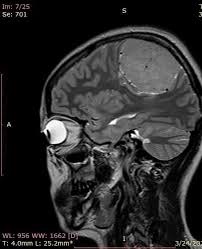

Монголд анх удаа тархины хорт хавдрыг унтуулгагүй хагалгаагаар авсан Улсын гуравдугаар төв эмнэлгийн Мэдрэлийн мэс заслын тасгийн их эмч Д.Энхболдтой ярилцлаа.

-Тархины хорт хавдрыг унтуулгагүй авсан хагалгааныхаа тухай ярьж өгөхгүй юү?

-Хүний тархин дахь хорт хавдрыг унтуулахгүйгээр сэрүүн байлгаж авч болдог арга бий. Түүнийг мэргэжлийн хэллэгээр унтуулгагүй хагалгаа буюу ширүүн хагалгаа гэж нэрлэдэг. Тархийг хүний биеийн төв хэсэг гэж хэлж болно. Хүний тархин доторх хавдрыг авч байх үедээ мэдрэлийн хэсгүүдийг нь гэмтээхгүйн тулд өвчтөнтэйгөө ярьж хөөрөх, хөл, гарыг нь хөдөлгөх зэргээр ажиллаж, хагалгаа хийдэг юм.

| Монголд анх удаа тархины хорт хавдрыг унтуулгагүй авсан эмч Д.ЭНХБОЛД: Мэс заслын эмчид ганцхан л боломж байдаг |